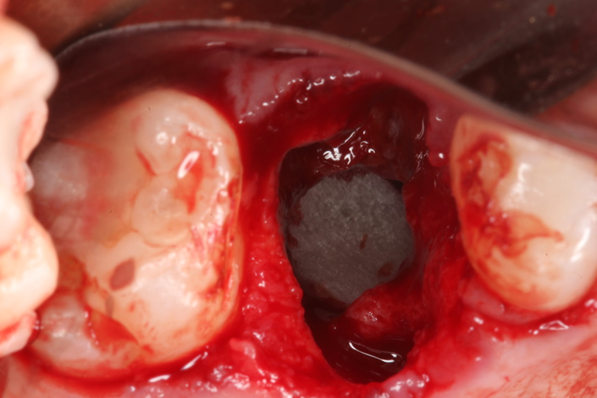

Paciente C.B.F.J., 33 anos, leucoderma, não-fumante e em boas condições de saúde sistêmica, relatou sensibilidade dolorosa durante mastigação no elemento 26, que já possuía tratamento endodôntico, pinos metálicos intrarradiculares e coroa metalocerâmica (Figura 1). Foi solicitada tomografia computadorizada de feixe cônico, na qual a imagem sugeriu fratura radicular na região da furca, descontinuidade óssea da cortical de seio maxilar e opacificação parcial do seio maxilar esquerdo (Figura 2). Foi realizada a exodontia e pôde-se confirmar a comunicação oroantral (Figura 3). Após curetagem do alvéolo, sem preocupação em curetar e remover a lesão cística sinusal, uma barreira reabsorvível foi recortada e posicionada no fundo do alvéolo para obliterar a descontinuidade óssea e impedir que células de tecido mole oriundas da cavidade sinusal invadissem a região alveolar (Figura 4). O alvéolo foi preenchido totalmente por coágulo sanguíneo do paciente (Figura 5) e o alvéolo foi selado por uma barreira não-reabsorvível (Figura 6), impedindo a invasão de fibroblastos do tecido gengival para dentro do alvéolo. Após duas semanas, a barreira estava estável e, então, foi removida, desnudando um tecido de granulação osteoblastogênico (Figura 7).